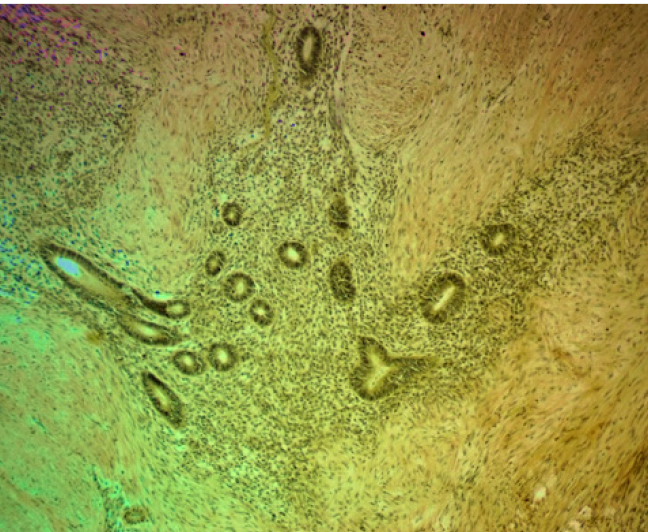

Очаговая экспрессия α-SMA была обнаружена в цитогенной строме очагов экстрагенитального эндометриоза в концентрических пролифератах миофибробластов по типу микроскопических лейомиом. В мышечном слое кишки наблюдалась положительная экспрессия α-SMA, которая повторяла ход мышечных волокон, деформируя стенку кишки в местах локализации очагов эндометриоза (рис. 4).